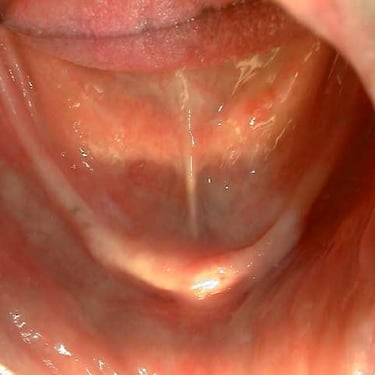

Atrofia ósea alveolar

La atrofia ósea alveolar es la pérdida de hueso en la mandíbula o el maxilar debido a la ausencia prolongada de dientes.

Los pacientes pueden notar que sus encías están hundidas y que las dentaduras no encajan bien.

El tratamiento puede incluir injertos óseos para preparar el sitio para la colocación de implantes.